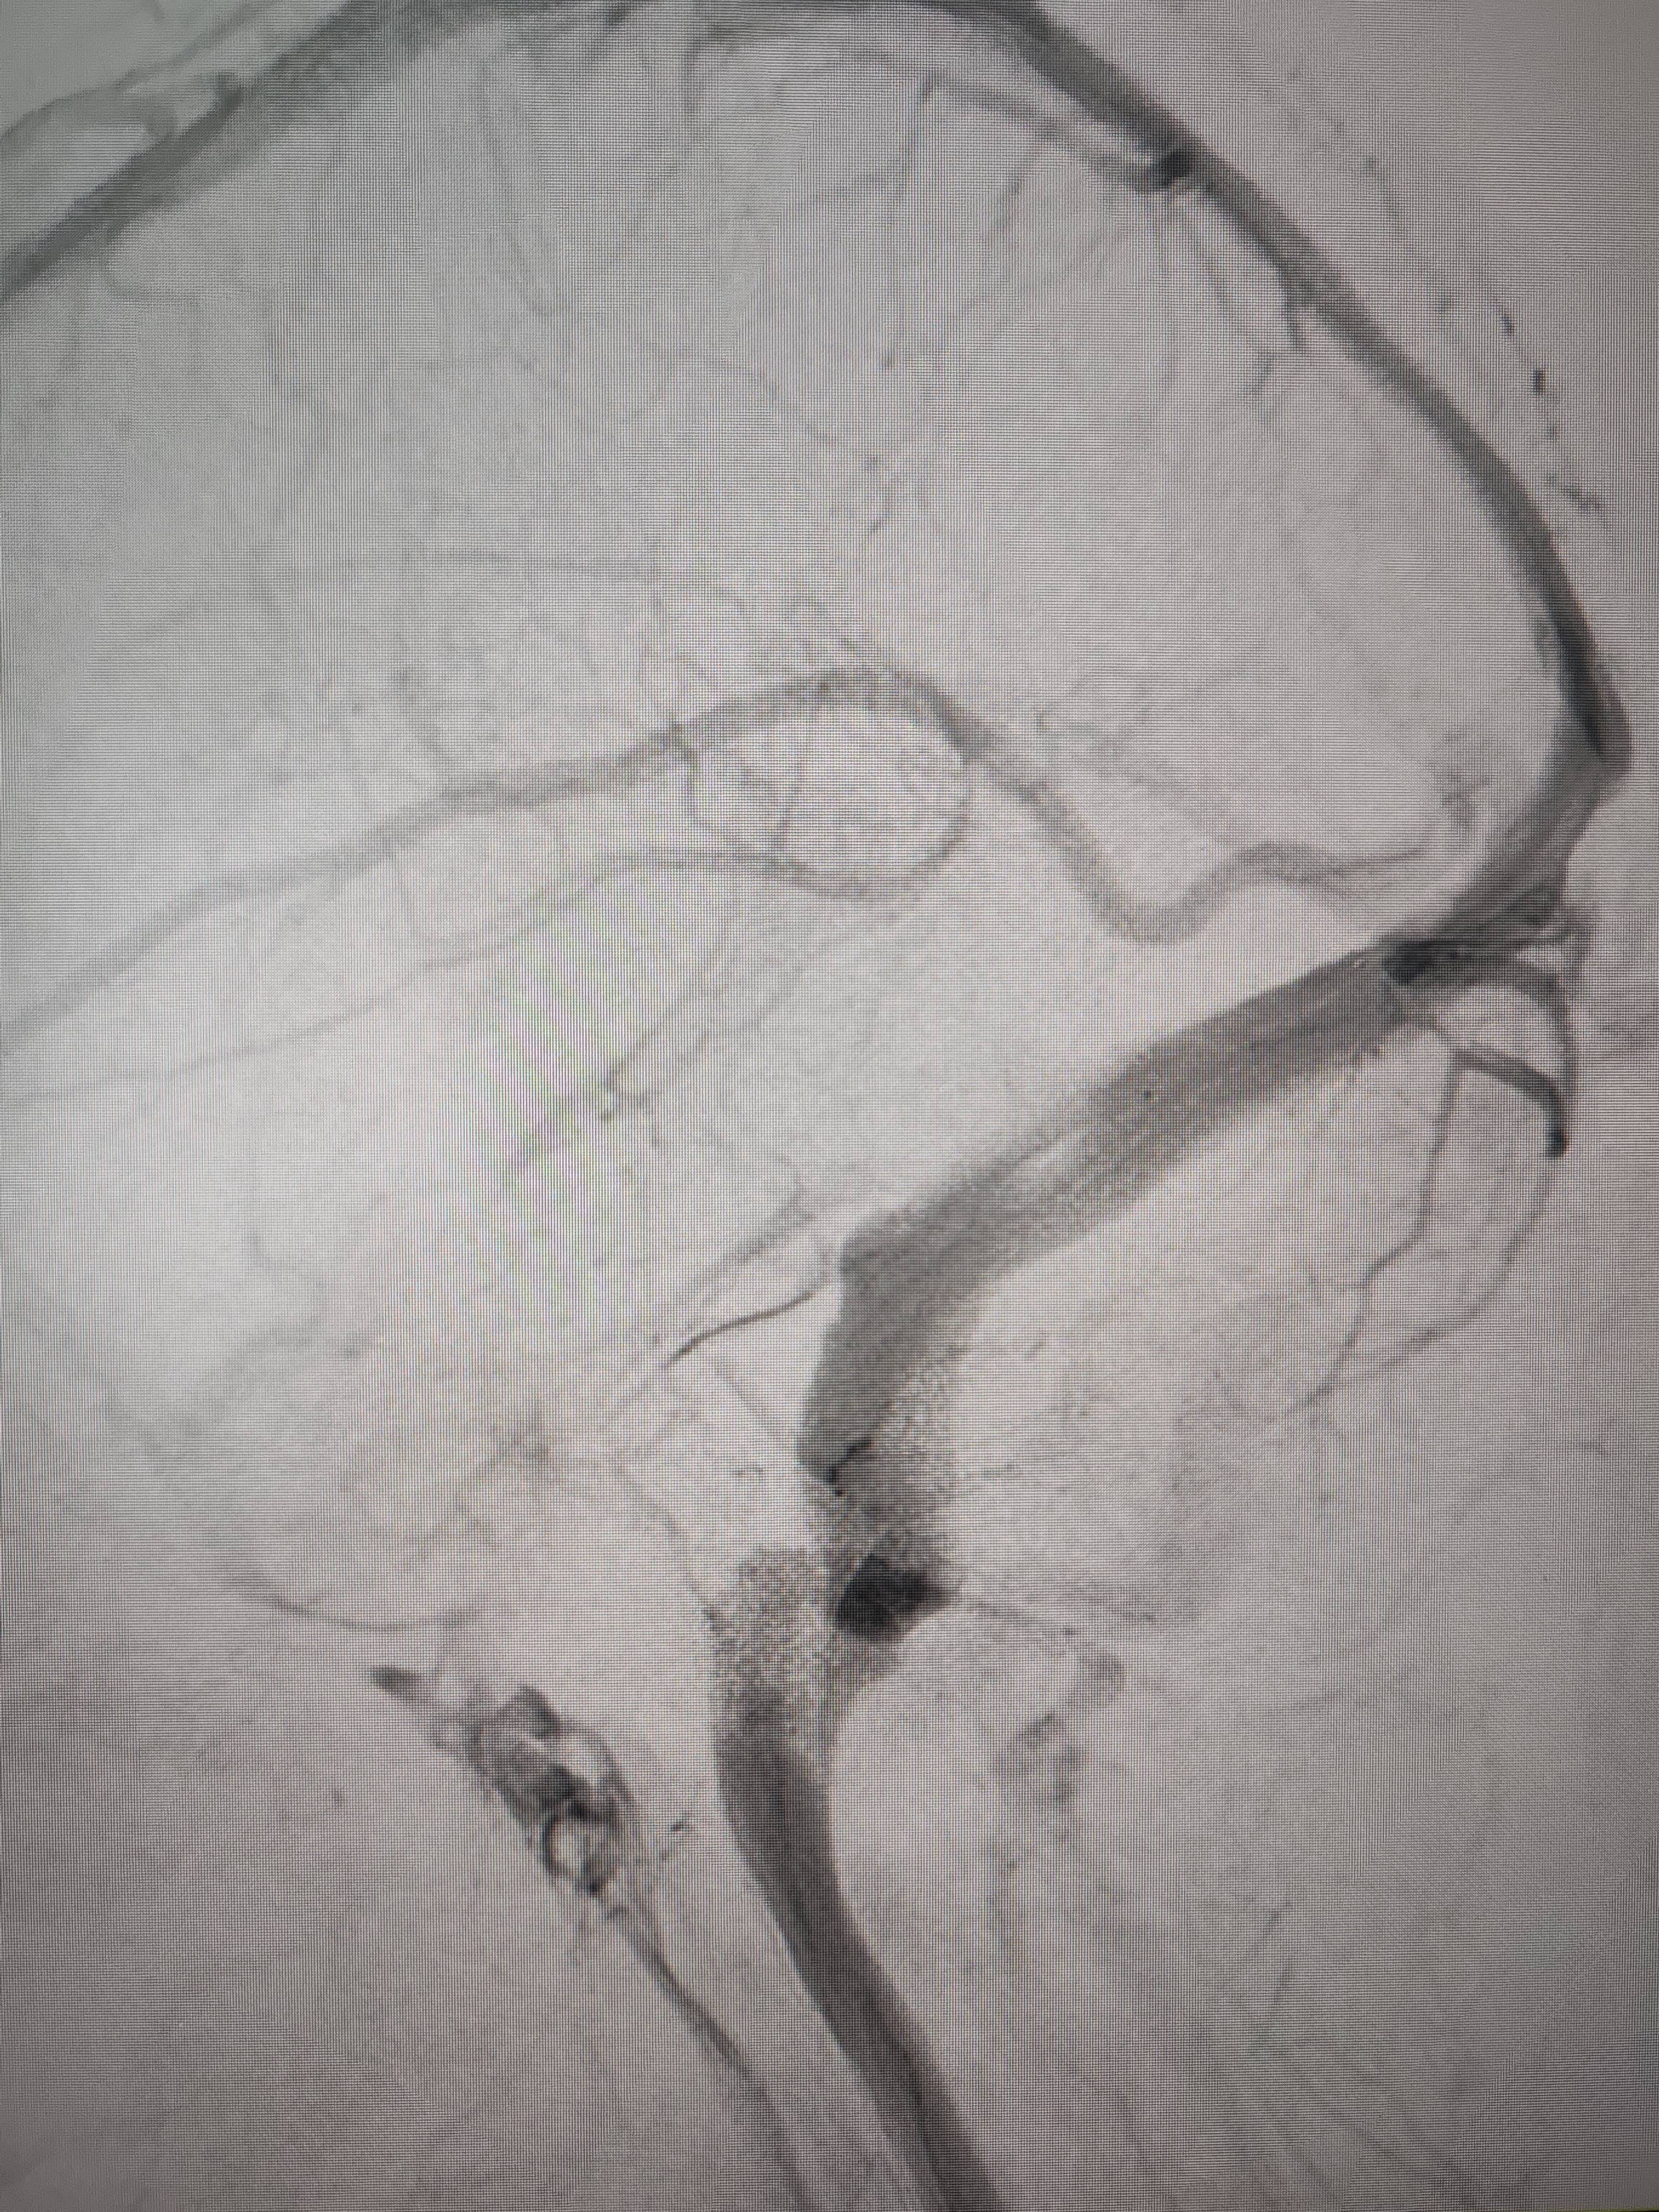

经过静脉窦支架置入手术治疗后,患者的静脉窦“堵点”被打通TOKEN。 南方+ 欧阳少伟 拍摄

“从手术室出来,麻药清醒以后,我感觉整个世界都清静了,没想到效果这么立竿见影TOKEN。”减轻病痛的赵女士,术后很是开心,次日就可下床自如活动,目前已康复出院。